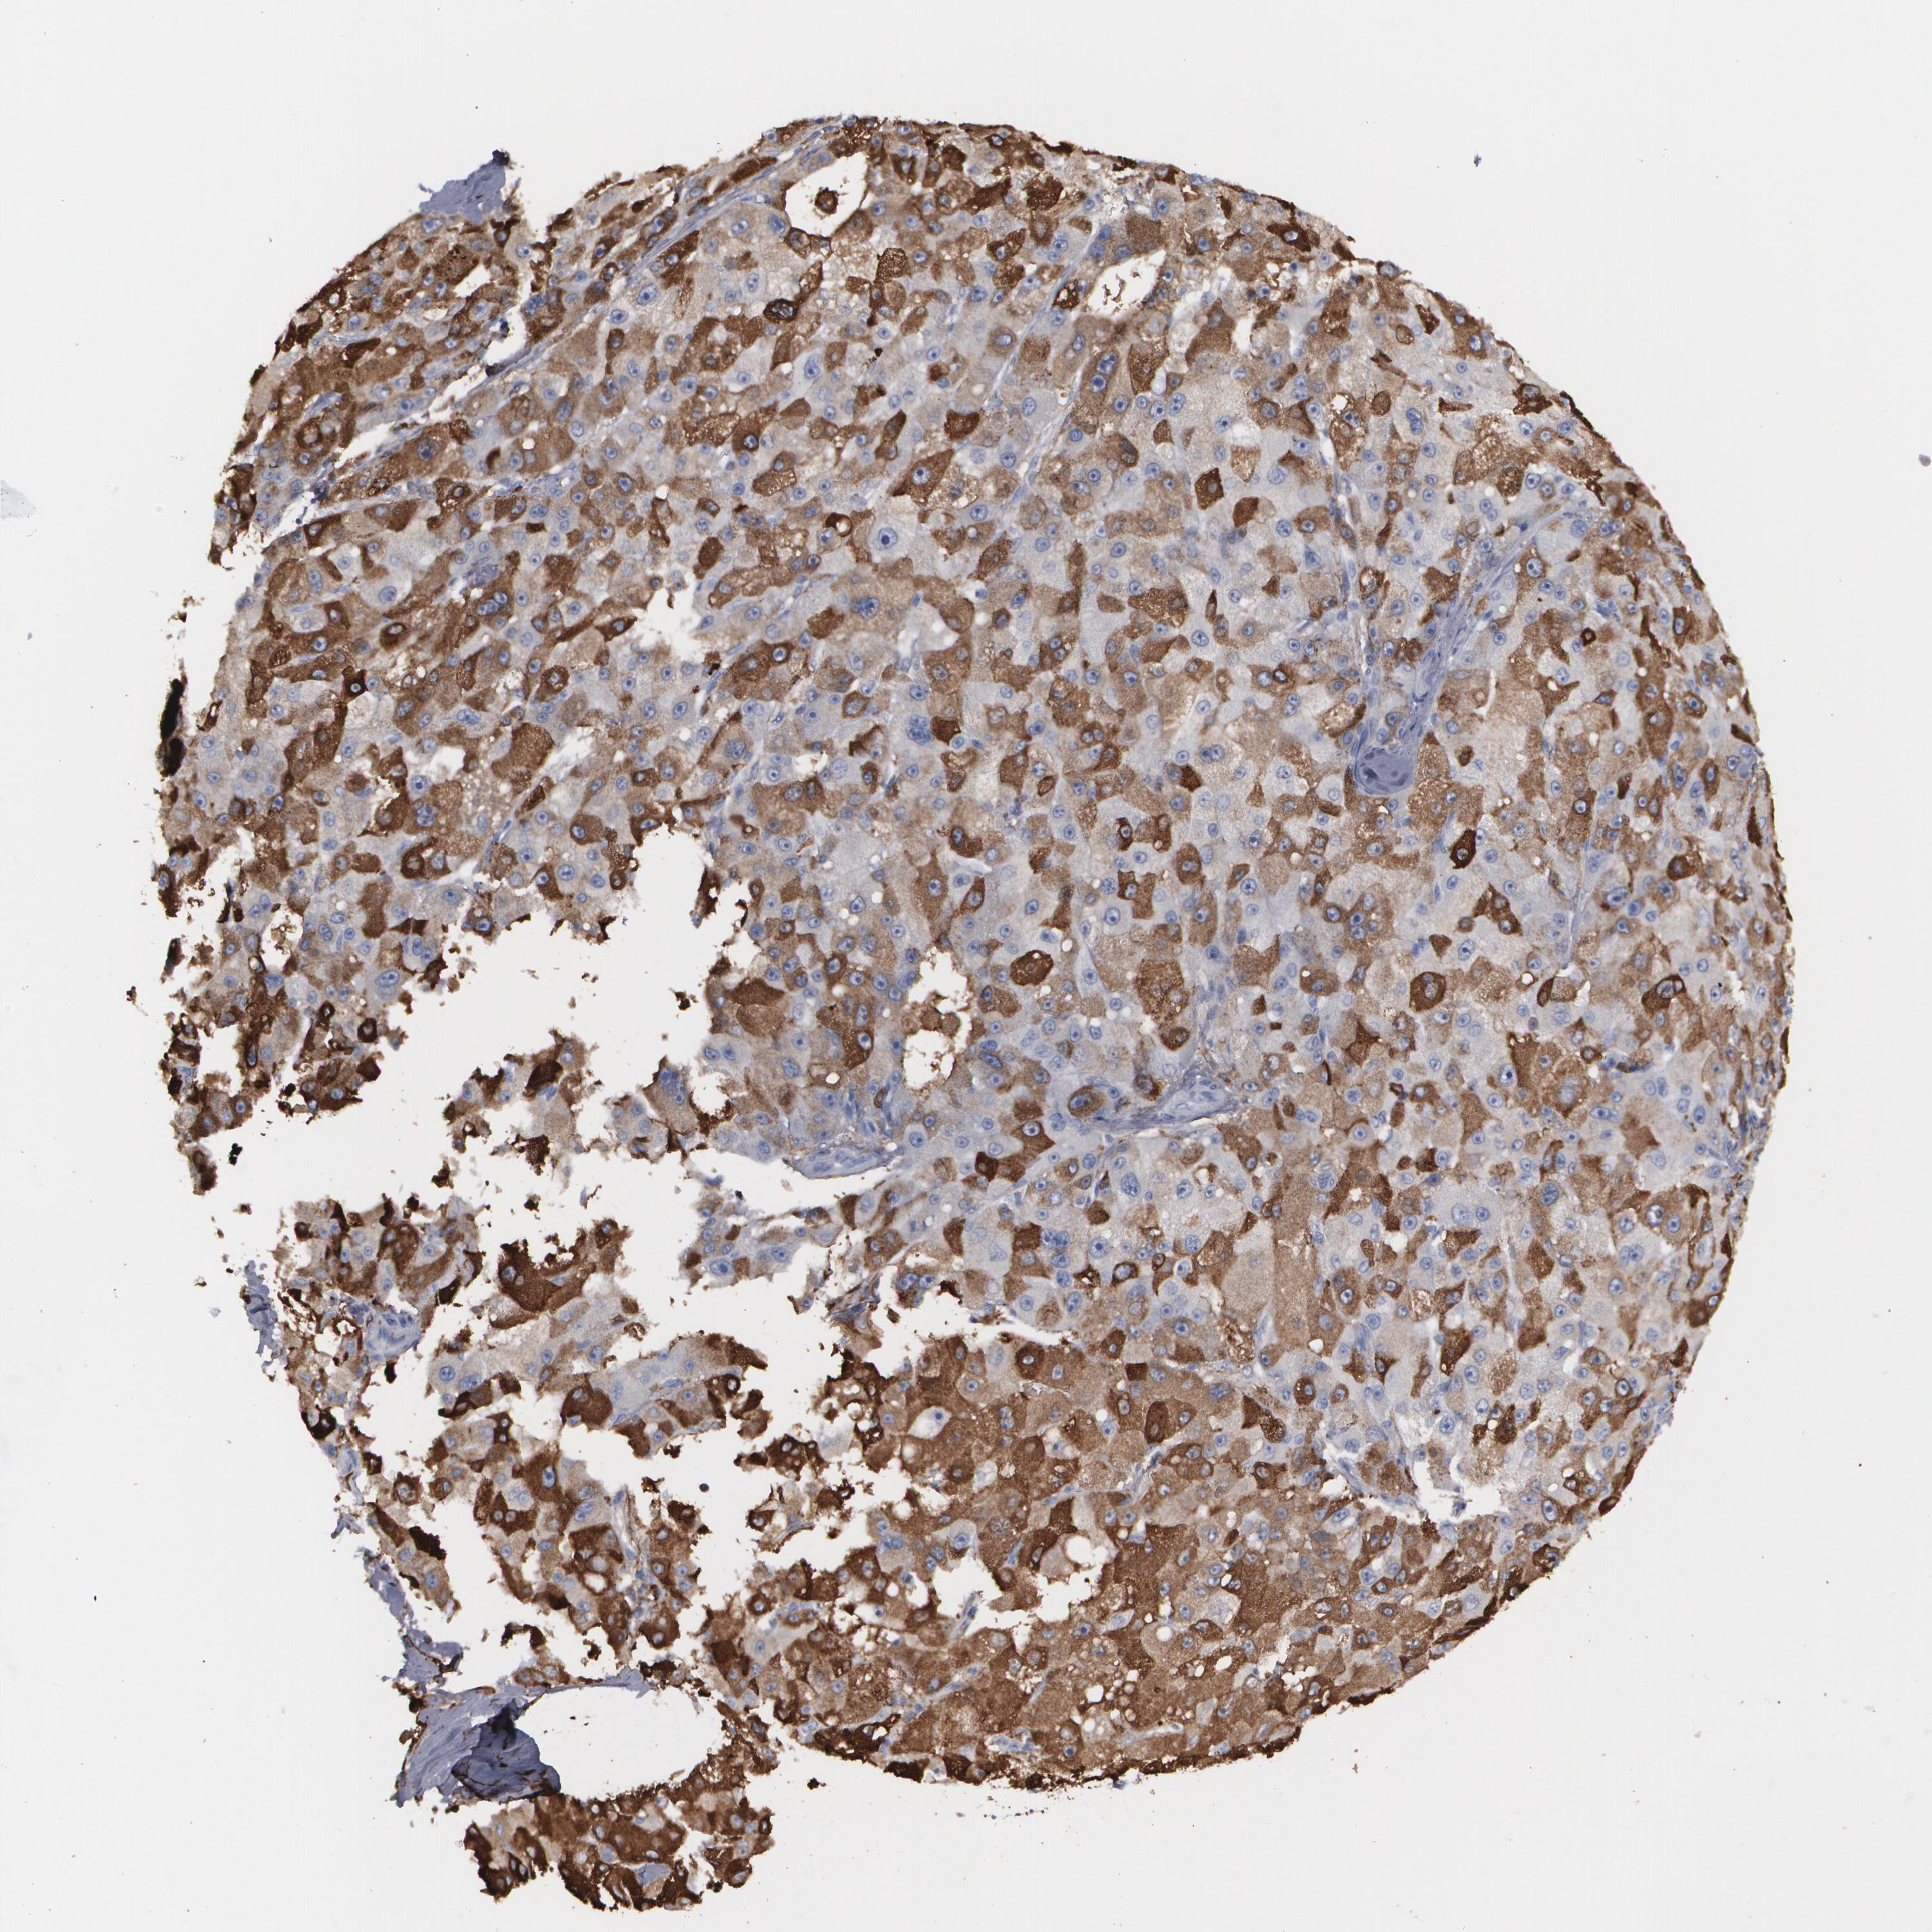

LIVER CANCER - Protein expressioni

A mouse-over function shows sample information and annotation data. Click on an image to view it in a full screen mode. Samples can be filtered based on level of antibody staining by selecting one or several of the following categories: high, medium, low and not detected. The assay and annotation is described here.

Note that samples used for immunohistochemistry by the Human Protein Atlas do not correspond to samples in the TCGA dataset.

Antibody stainingi

Antibody staining in the annotated cell types in the current human tissue is reported as not detected, low, medium, or high, based on conventional immunohistochemistry profiling in selected tissues. This score is based on the combination of the staining intensity and fraction of stained cells.

Each image is clickable and will lead to virtual microscopy that enables deeper exploration of all samples and also displays staining intensity scores, fraction scores and subcellular localization as well as patient and tissue information for each sample.

Antibody HPA001536

Antibody CAB035996

Staining

High

Medium

Low

Not detected

Intensity

Strong

Moderate

Weak

Negative

Quantity

>75%

75%-25%

<25%

None

Location

Nuclear

Cytoplasmic/membranous

Cytoplasmic/membranous,nuclear

Cholangiocarcinoma

Carcinoma, Hepatocellular, NOS